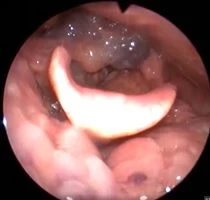

Клинический случай №2. Хирургическое лечение двустороннего паралича гортани с применением лазера 445 нм.

В нашей клинике лечение этих пациентов проводится по методу, разработанному Кривопаловым А. А., который хорошо себя зарекомендовал.

После операции проявления воспаления минимальны. Через месяц после вмешательства пациенты готовы перейти к следующему этапу восстановления – занятиям с логопедом.

Рис 2А. Двусторонний паралич гортани. До операции.

Рис 2Б. Двусторонний паралич гортани. На 7 сутки после операции.

Рис 2В. Двусторонний паралич гортани. На 1 месяц после операции.